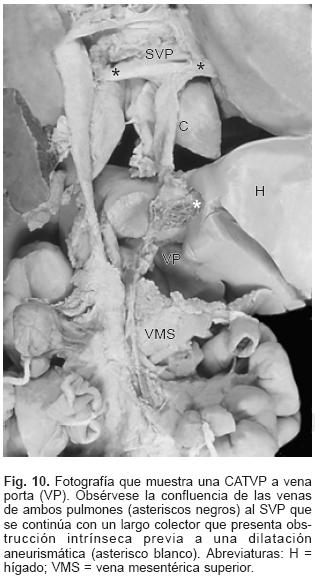

En la CATVP al atrio derecho el SVP se integra en la parte posterosuperior de esta cámara a través de un colector muy corto (Fig. 7). En el sitio de conexión al seno venoso coronario el colector venoso desembocó en el extremo izquierdo de dicho seno el cual estuvo dilatado (Figs. 2 y 8). El orificio de desembocadura del seno venoso coronario en el atrio derecho fue muy amplio y se situó por debajo de la comunicación interatrial (Fig. 9). En un espécimen existió estrechez intrínseca del colector en el sitio en que se unió al seno venoso coronario. En la conexión anómala infradiafragmática el SVP recibió las venas de ambos pulmones y se continuó con un colector largo que acompañó al esófago, atravesó el hiato esofágico y descendió hasta desembocar en la vena porta justo antes de penetrar al hígado (Fig. 10). Todos los corazones de este grupo presentaron obstrucción extrínseca a nivel del hiato esofágico y en dos especímenes se agregó obstrucción intrínseca en el colector antes de su desembocadura en la vena porta (Fig. 10).